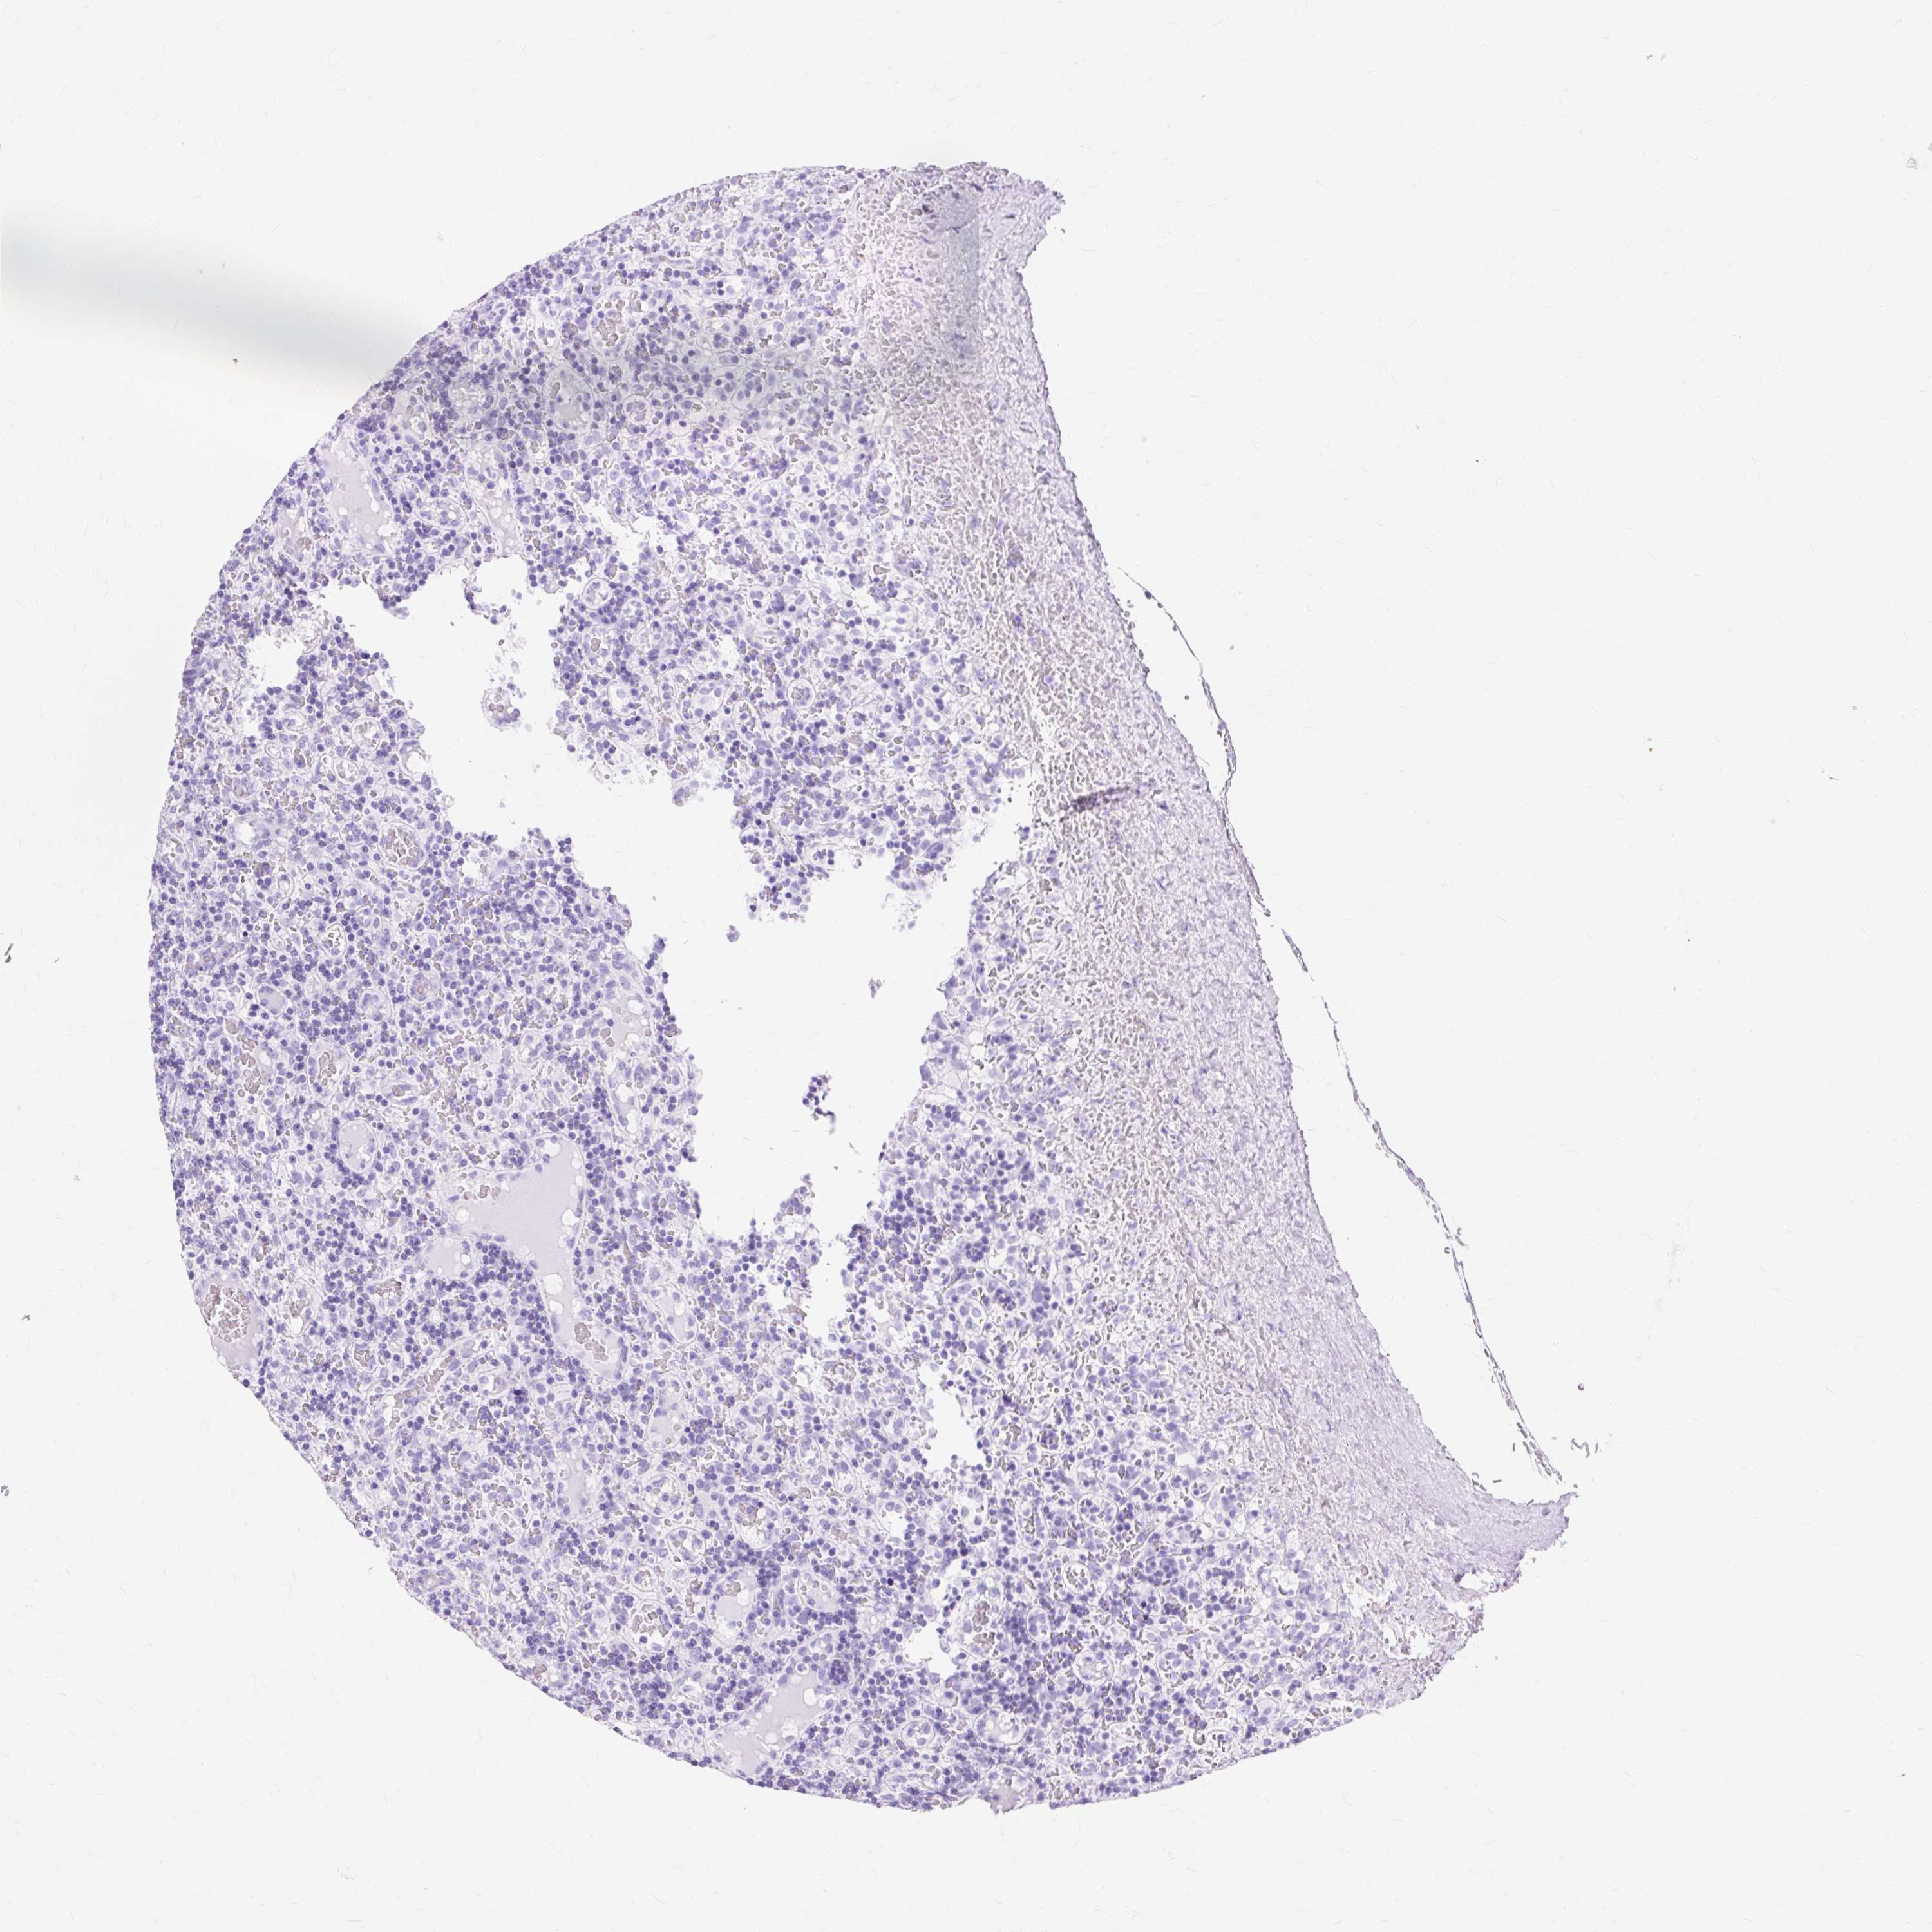

CANCER LYMPHOMA Show tissue menu

LYMPHOMA - Protein expressioni

A mouse-over function shows sample information and annotation data. Click on an image to view it in a full screen mode. Samples can be filtered based on level of antibody staining by selecting one or several of the following categories: high, medium, low and not detected. The assay and annotation is described here.

Each image is clickable and will lead to virtual microscopy that enables deeper exploration of all samples and also displays staining intensity scores, fraction scores and subcellular localization as well as patient and tissue information for each sample.

Antibody HPA049222

Antibody CAB002300

Hodgkin's disease, NOS

Malignant lymphoma, non-Hodgkin's type, High grade

Malignant lymphoma, non-Hodgkin's type, Low grade